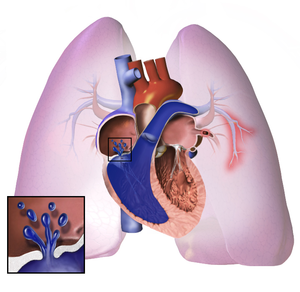

Pulmonary hypertension (PH or PHTN) is a condition of increased blood pressure within the arteries of the lungs.[7] Symptoms include shortness of breath, syncope, tiredness, chest pain, swelling of the legs, and a fast heartbeat.[7][2] The condition may make it difficult to exercise.[7] Onset is typically gradual.[8]

The cause is often unknown.[1] Risk factors include a family history, prior blood clots in the lungs, HIV/AIDS, sickle cell disease, cocaine use, chronic obstructive pulmonary disease, sleep apnea, living at high altitudes, and problems with the mitral valve.[5][4] The underlying mechanism typically involves inflammation of the arteries in the lungs.[5] Diagnosis involves first ruling out other potential causes.[1]

The pathogenesis of pulmonary arterial hypertension (WHO Group I) involves the narrowing of blood vessels connected to and within the lungs. This makes it harder for the heart to pump blood through the lungs, much as it is harder to make water flow through a narrow pipe as opposed to a wide one. Over time, the affected blood vessels become stiffer and thicker, in a process known as fibrosis. The mechanisms involved in this narrowing process include vasoconstriction, thrombosis, and vascular remodeling (excessive cellular proliferation, fibrosis, and reduced apoptosis/programmed cell death in the vessel walls, caused by inflammation, disordered metabolism and dysregulation of certain growth factors).[24][25] Over time, vascular remodeling causes the affected blood vessels to become progressively stiffer and thicker. This further increases the blood pressure within the lungs and impairs their blood flow. In common with other types of pulmonary hypertension, these changes result in an increased workload for the right side of the heart.[11][26] The right ventricle is normally part of a low pressure system, with systolic ventricular pressures that are lower than those that the left ventricle normally encounters. As such, the right ventricle cannot cope as well with higher pressures, and although right ventricular adaptations (hypertrophy and increased contractility of the heart muscle) initially help to preserve stroke volume, ultimately these compensatory mechanisms are insufficient; the right ventricular muscle cannot get enough oxygen to meet its needs and right heart failure follows.[11][25][26] As the blood flowing through the lungs decreases, the left side of the heart receives less blood. This blood may also carry less oxygen than normal. Therefore, it becomes harder and harder for the left side of the heart to pump to supply sufficient oxygen to the rest of the body, especially during physical activity.[27][28][19]